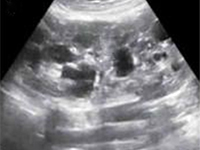

OtherIt’s a case presentaƟon of two siblings: a 17-year-old girl and her 15-year-old brother who both developed speech and swallowing difficulƟes, shaking hands and decreased muscle tone at the age of 4. Results of laboratory tests only indicated a tendency to low potassium and magnesium serum concentraƟons. The siblings were diagnosed for cerebellar-extrapyramidal syndrome. AŌer several years of follow-up the paƟent were referred to the Pediatric Nephrology Hospital because of hyperechogenic reflecƟons from renal parenchyma in abdominal ultrasound. Finally, tubulopathy was diagnosed. Diet supplements was included as a result of a persistent electrolyte imbalance, with a posiƟve therapeuƟc effect.